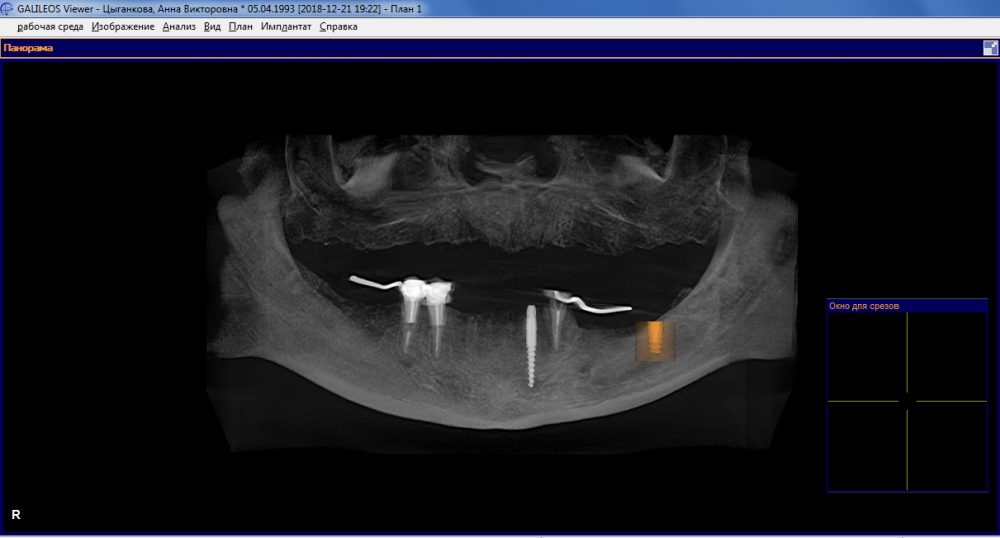

Имплантация, наращивание кости и съёмный протез - форум Стоматология.Су